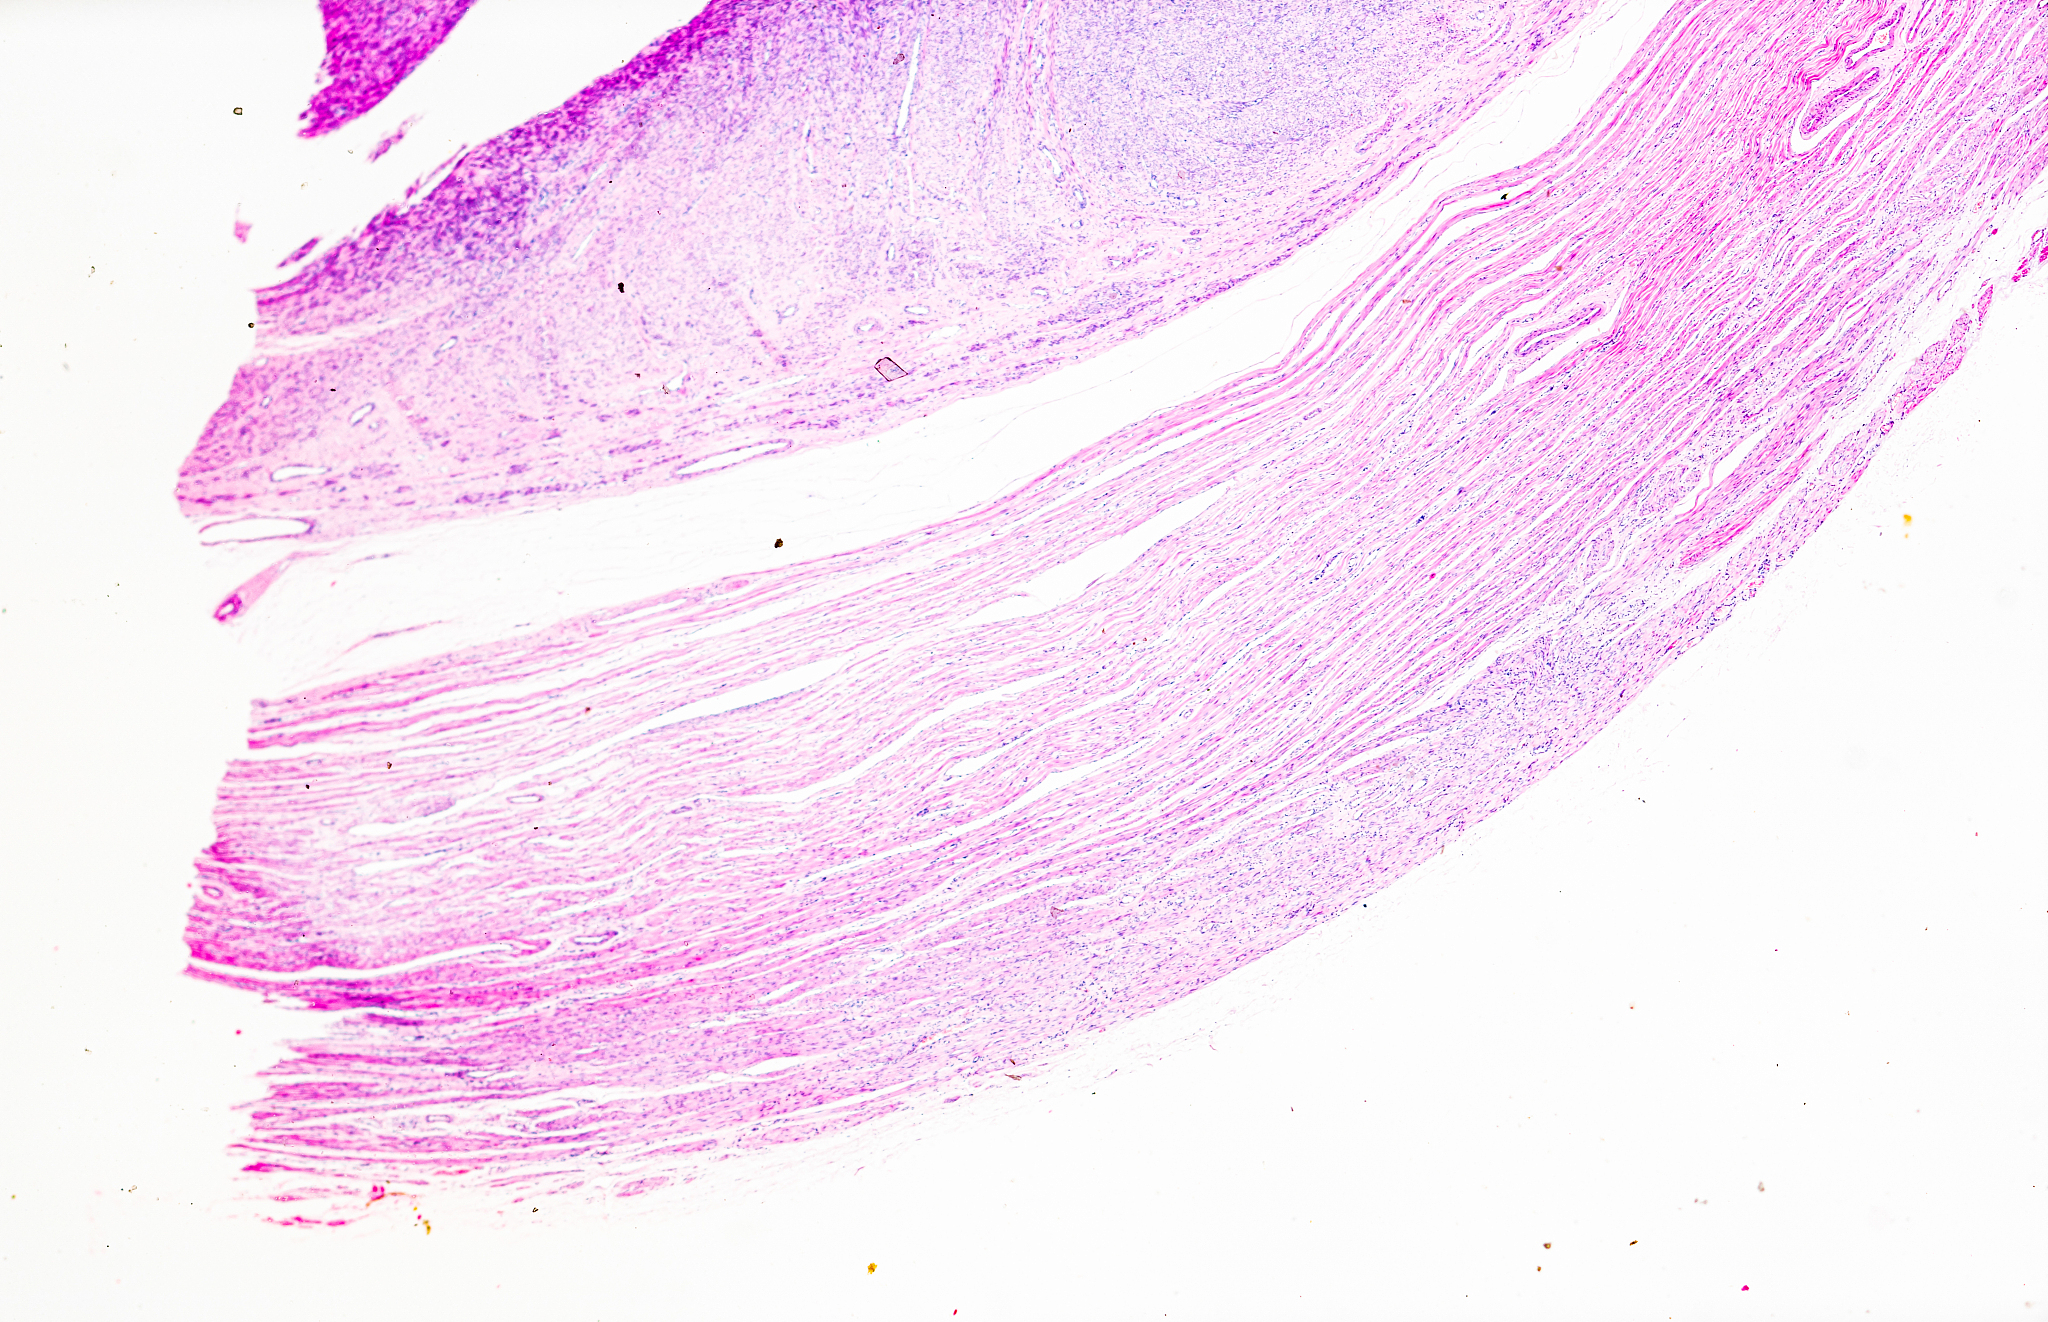

子宫平滑肌瘤,也称为子宫肌瘤或子宫纤维瘤,是一种常见的妇科良性肿瘤。它起源于子宫壁的平滑肌细胞,通常生长在子宫肌层内。子宫平滑肌瘤的大小、数量和位置可以因个体差异而有所不同。